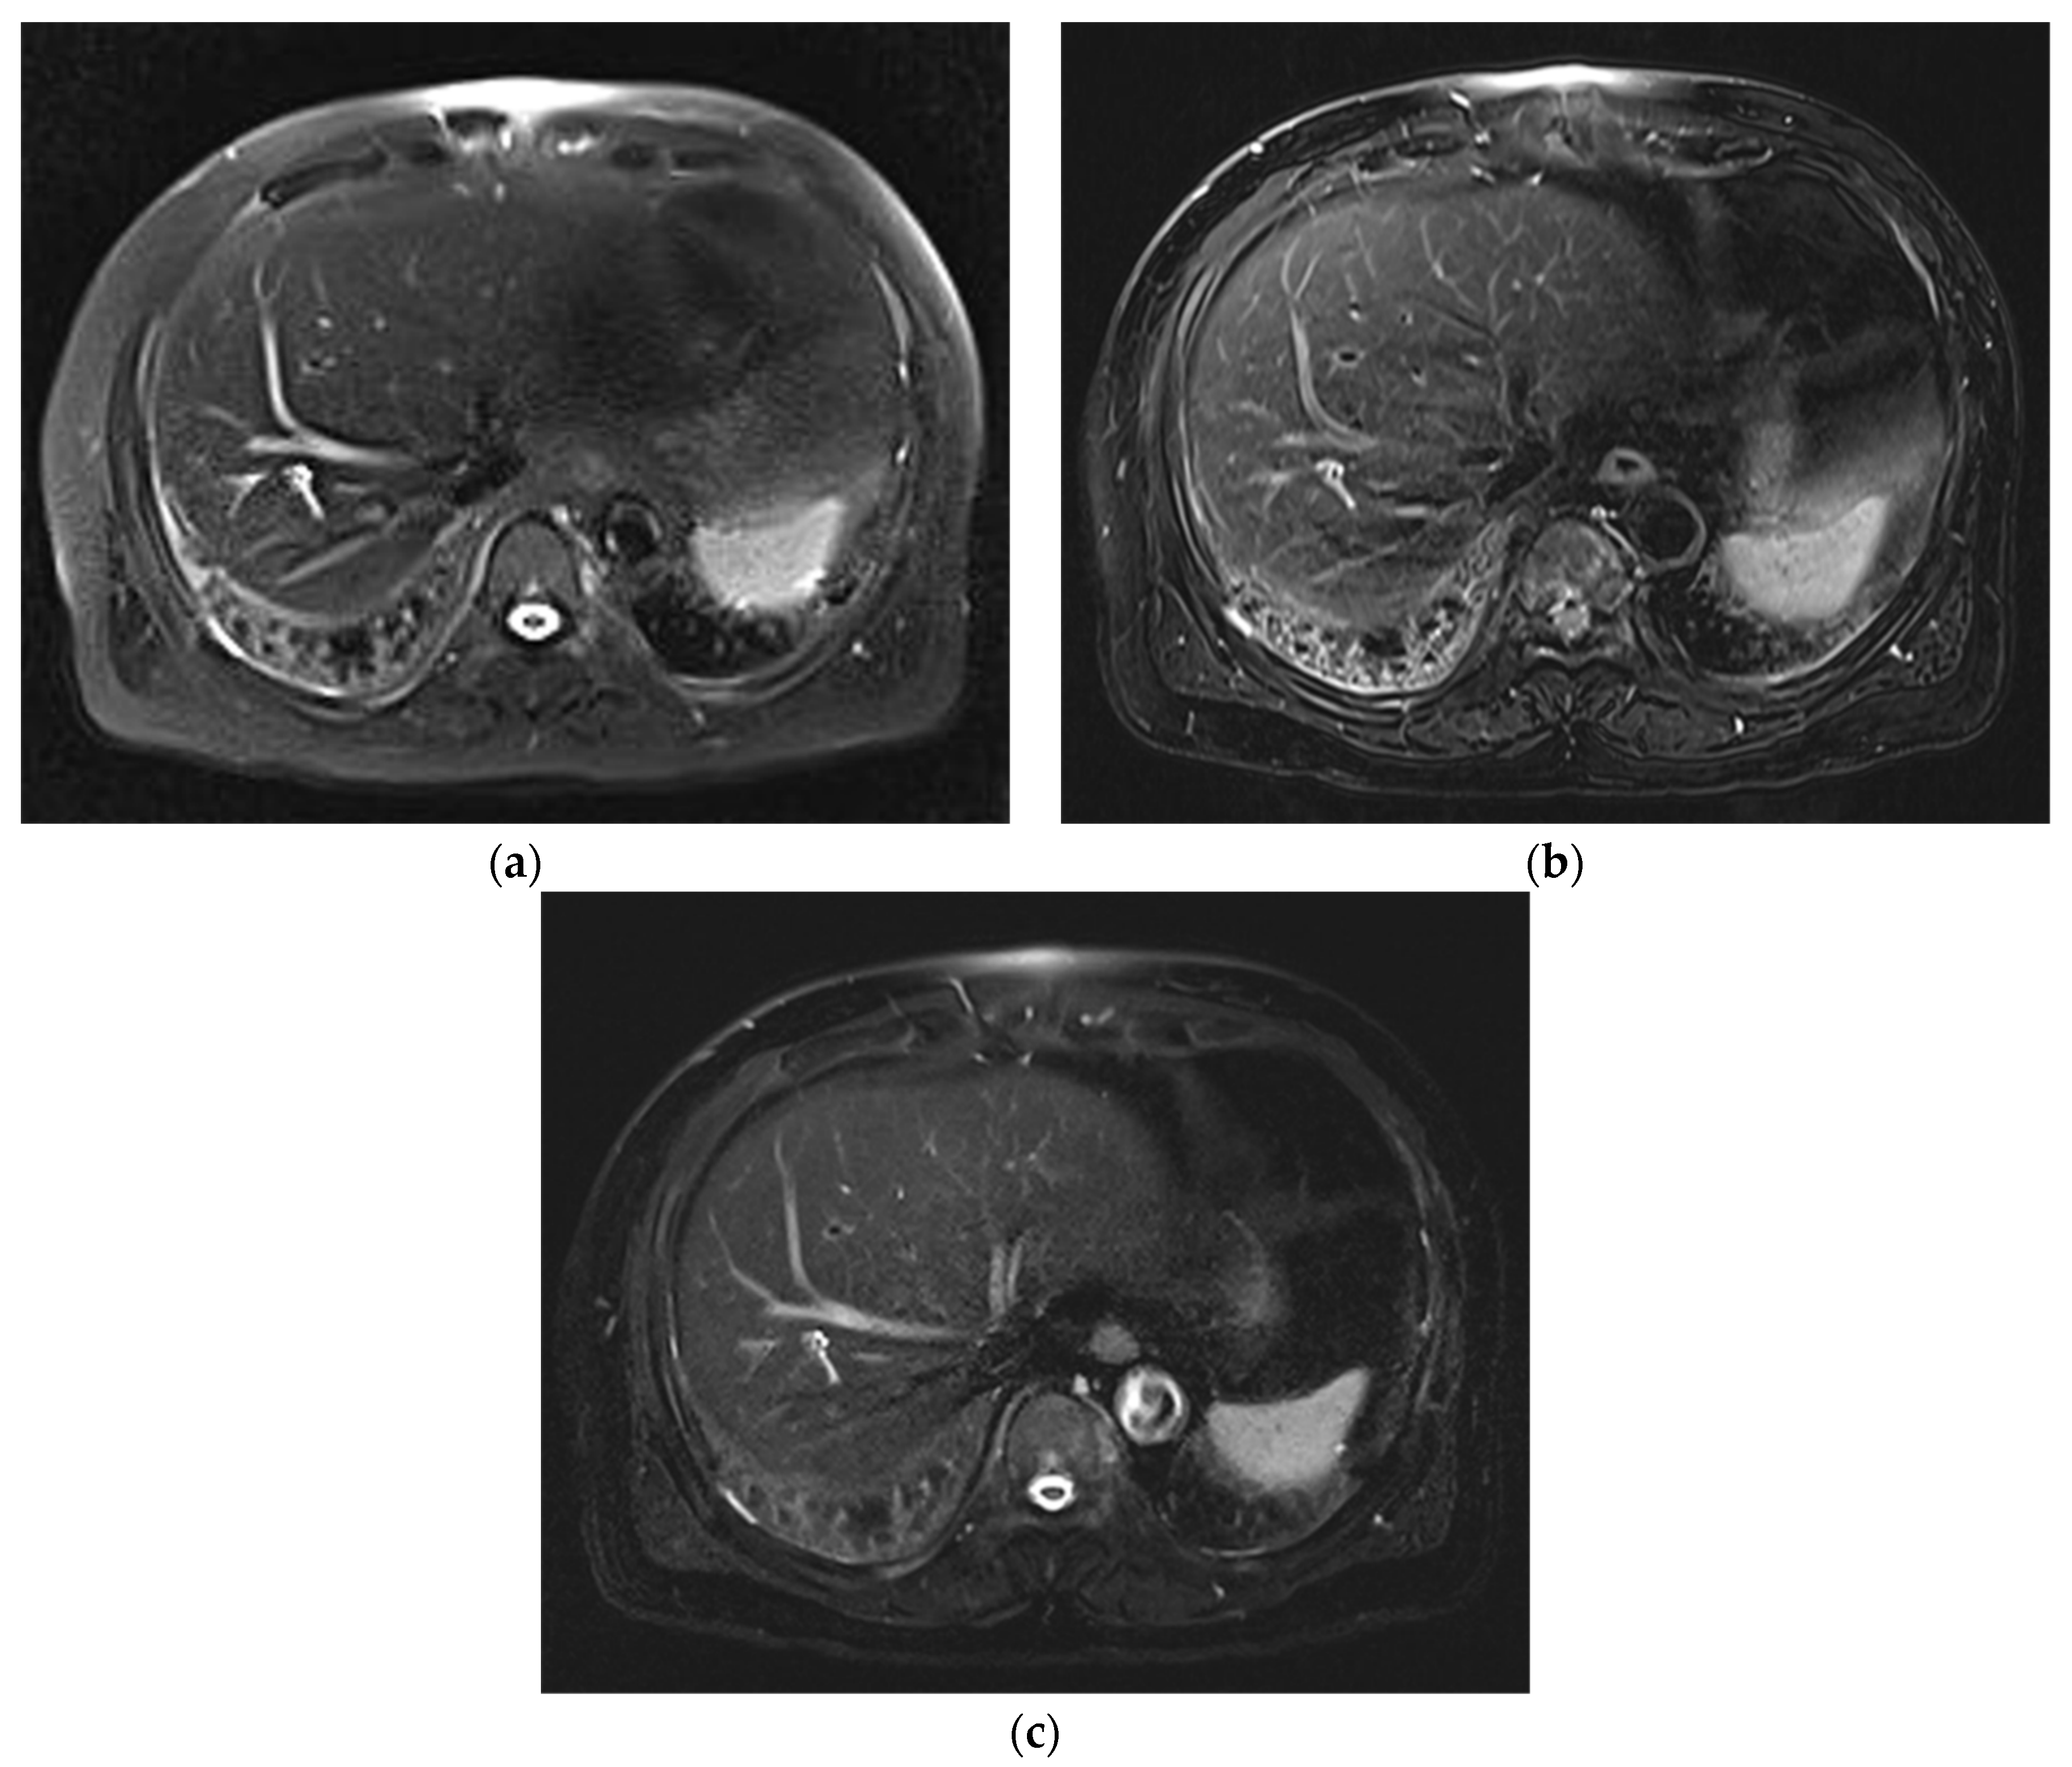

3.1. Subjective Image Quality

3.2. Lesion Assessment